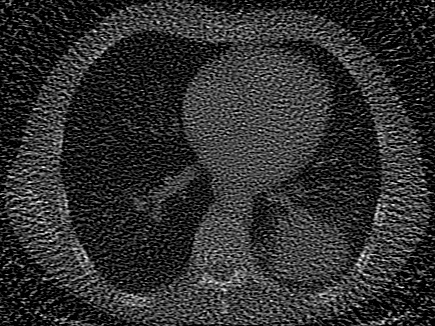

In addition to synthetic experiments, we evaluate each model on diverse tasks involving real-world 2D images and 3D volumes. These experiments assess the models’ ability to overfit, generalize, and solve inverse problems with natural signals. We use 10 images from DIV2K [27] to test image overfitting, super-resolution, and denoising at two different levels of Gaussian noise. We use 7 CT scans, including a 2D chest CT scan from Clark et al. [28] and 6 CT scans from the Generalizable Dose Prediction for Heterogeneous Multi-Cohort and Multi-Site Radiotherapy Planning challenge at AAPM 2025 [31], to evaluate performance in a classic underdetermined inverse problem, in which the task is to recover an image from undersampled X-ray projections. We evaluate volumetric performance using the occupancy function and surface of the 3D Stanford Dragon [29]. On both of these 3D signals we test both volume overfitting and super-resolution. Our real-data signals and tasks are summarized in the bottom half of Table˜1, with further details provided in Section˜5.4.

Computed Tomography (CT).

For CT experiments, we train models on a real chest CT slice from the dataset in Clark et al. [28], which was also used in WIRE [16]. The training data was 100 projection measurements of the original 326435 chest CT slice, forming a 100435 sinogram equivalent to approximately 30% of the total pixel count in the original image. Since this inverse problem is inherently underdetermined, we apply TV regularization in our Grid model. The TV hyperparameter was tuned using the classic Shepp-Logan phantom image [37] as a reconstruction target.